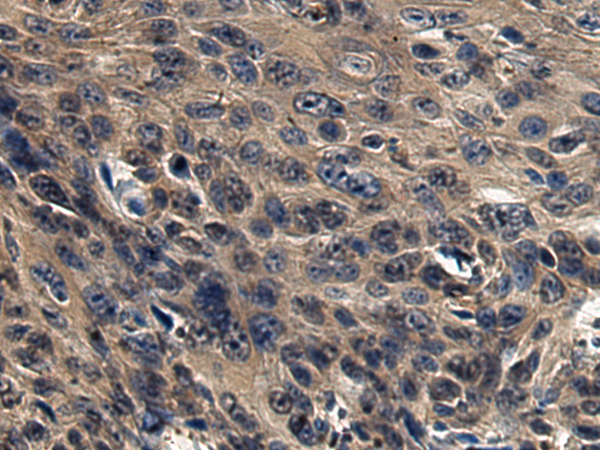

IHC positive control:

Human esophagus cancer

IHC Recommend dilution:

50-200